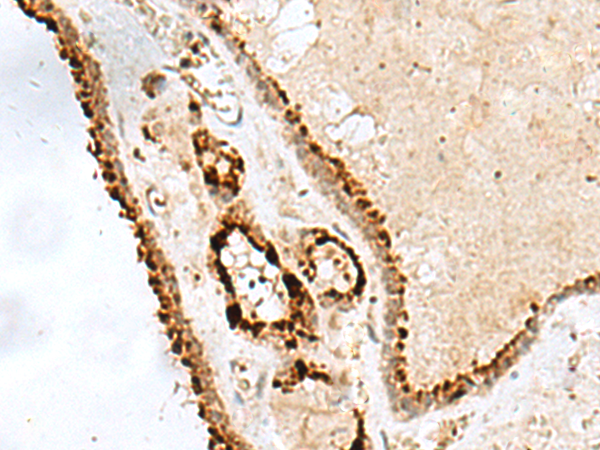

IHC positive control: |

Human thyroid cancer |